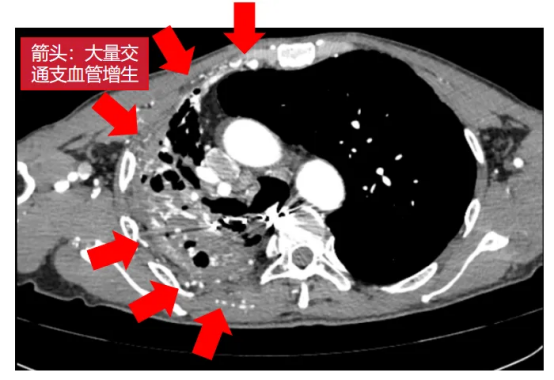

术前影像(左右滑动查看更多)

该患者为61岁男性,肺部病情错综复杂。4年前确诊肺结核后因治疗不规范,发展为“利福平耐药”结核,病情持续恶化。2年来反复咯血,虽经3次支气管动脉栓塞术暂时控制,但病灶顽固,收治入院时已形成多重诊断:毁损肺(右上)、右肺下叶鳞癌(背段)、肺曲霉菌病、陈旧性肺结核。其右肺上叶完全丧失功能,并与胸壁形成致密粘连,医学上称为“毁损肺”——胸外科领域公认的极高难度手术。

手术如期进行,然而打开胸腔的瞬间,其严峻程度远超预期:胸腔呈广泛致密黏连、完全闭锁,右肺上叶仿佛被水泥浇筑在胸壁上;肺表面及壁层胸膜布满大量脆弱的新生血管,呈现出“碰一下就出血”的凶险局面。